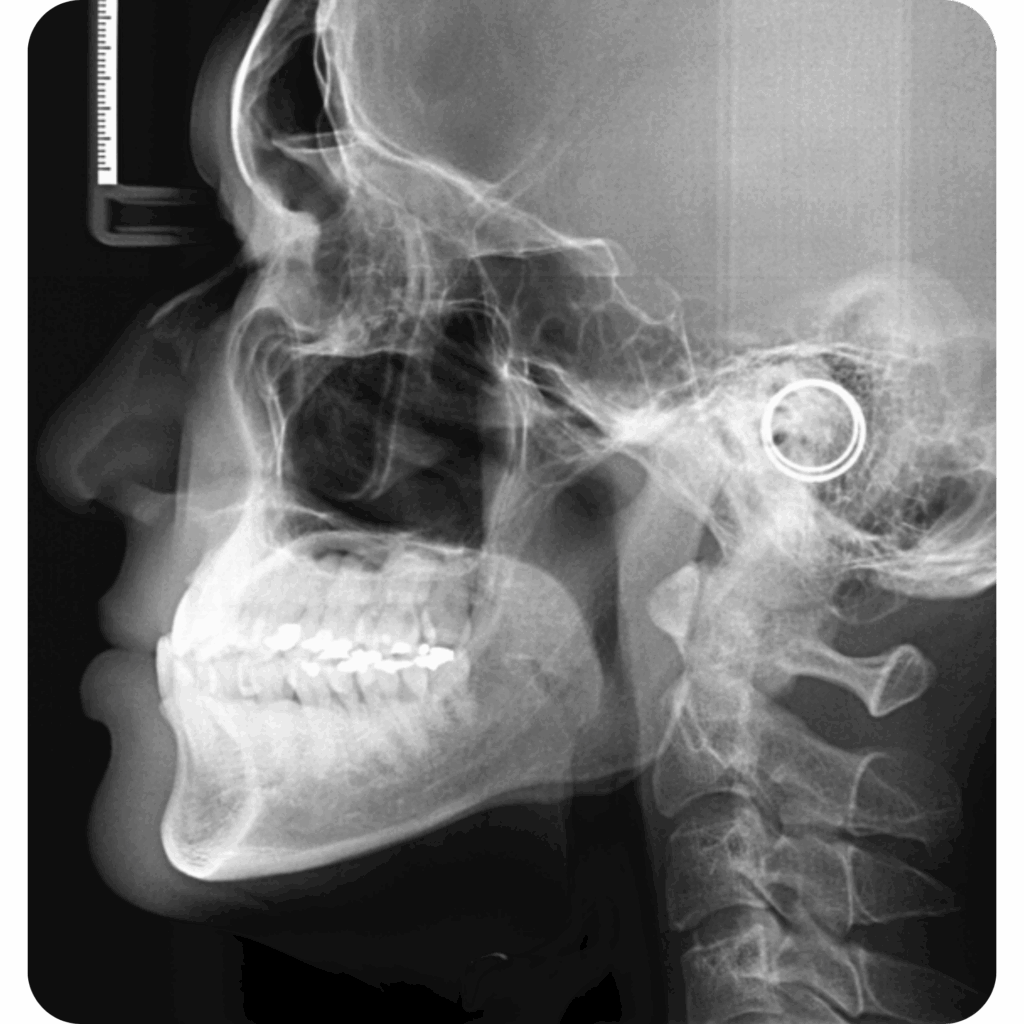

Radiografía lateral de cráneo, panorámica y carpal

Estudios iniciales para ortodoncia